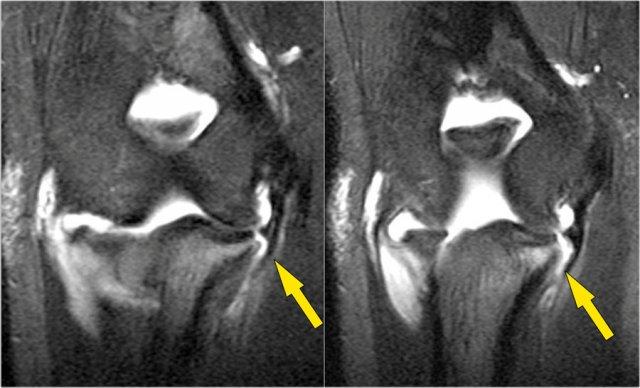

Đây là vận động viên ném bóng chày 18 tuổi với triệu chứng đau mặt trong khuỷu tay.

Có thể thấy một vết rách một phần tạo ra ‘dấu hiệu T’.

Đầu tiên hãy nghiên cứu các hình ảnh T2-fatsat theo mặt phẳng vành và sau đó tiếp tục đọc…

Lưu ý rằng bó trước còn nguyên vẹn và bám chắc vào củ sublime (mũi tên vàng).

Trên hai hình ảnh tiếp theo, có một số phù nề mô mềm và tín hiệu bất thường rõ hơn ở phía sau (mũi tên đỏ). Vì vậy, chúng tôi nghi ngờ có bệnh lý của bó sau.